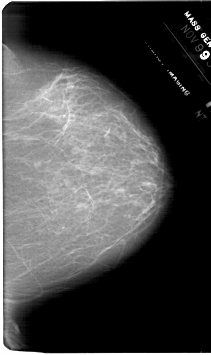

A_1768_1.LEFT_MLO

LEFT_MLO LINES 6301 PIXELS_PER_LINE 4216 BITS_PER_PIXEL 12 RESOLUTION 43.5 OVERLAY